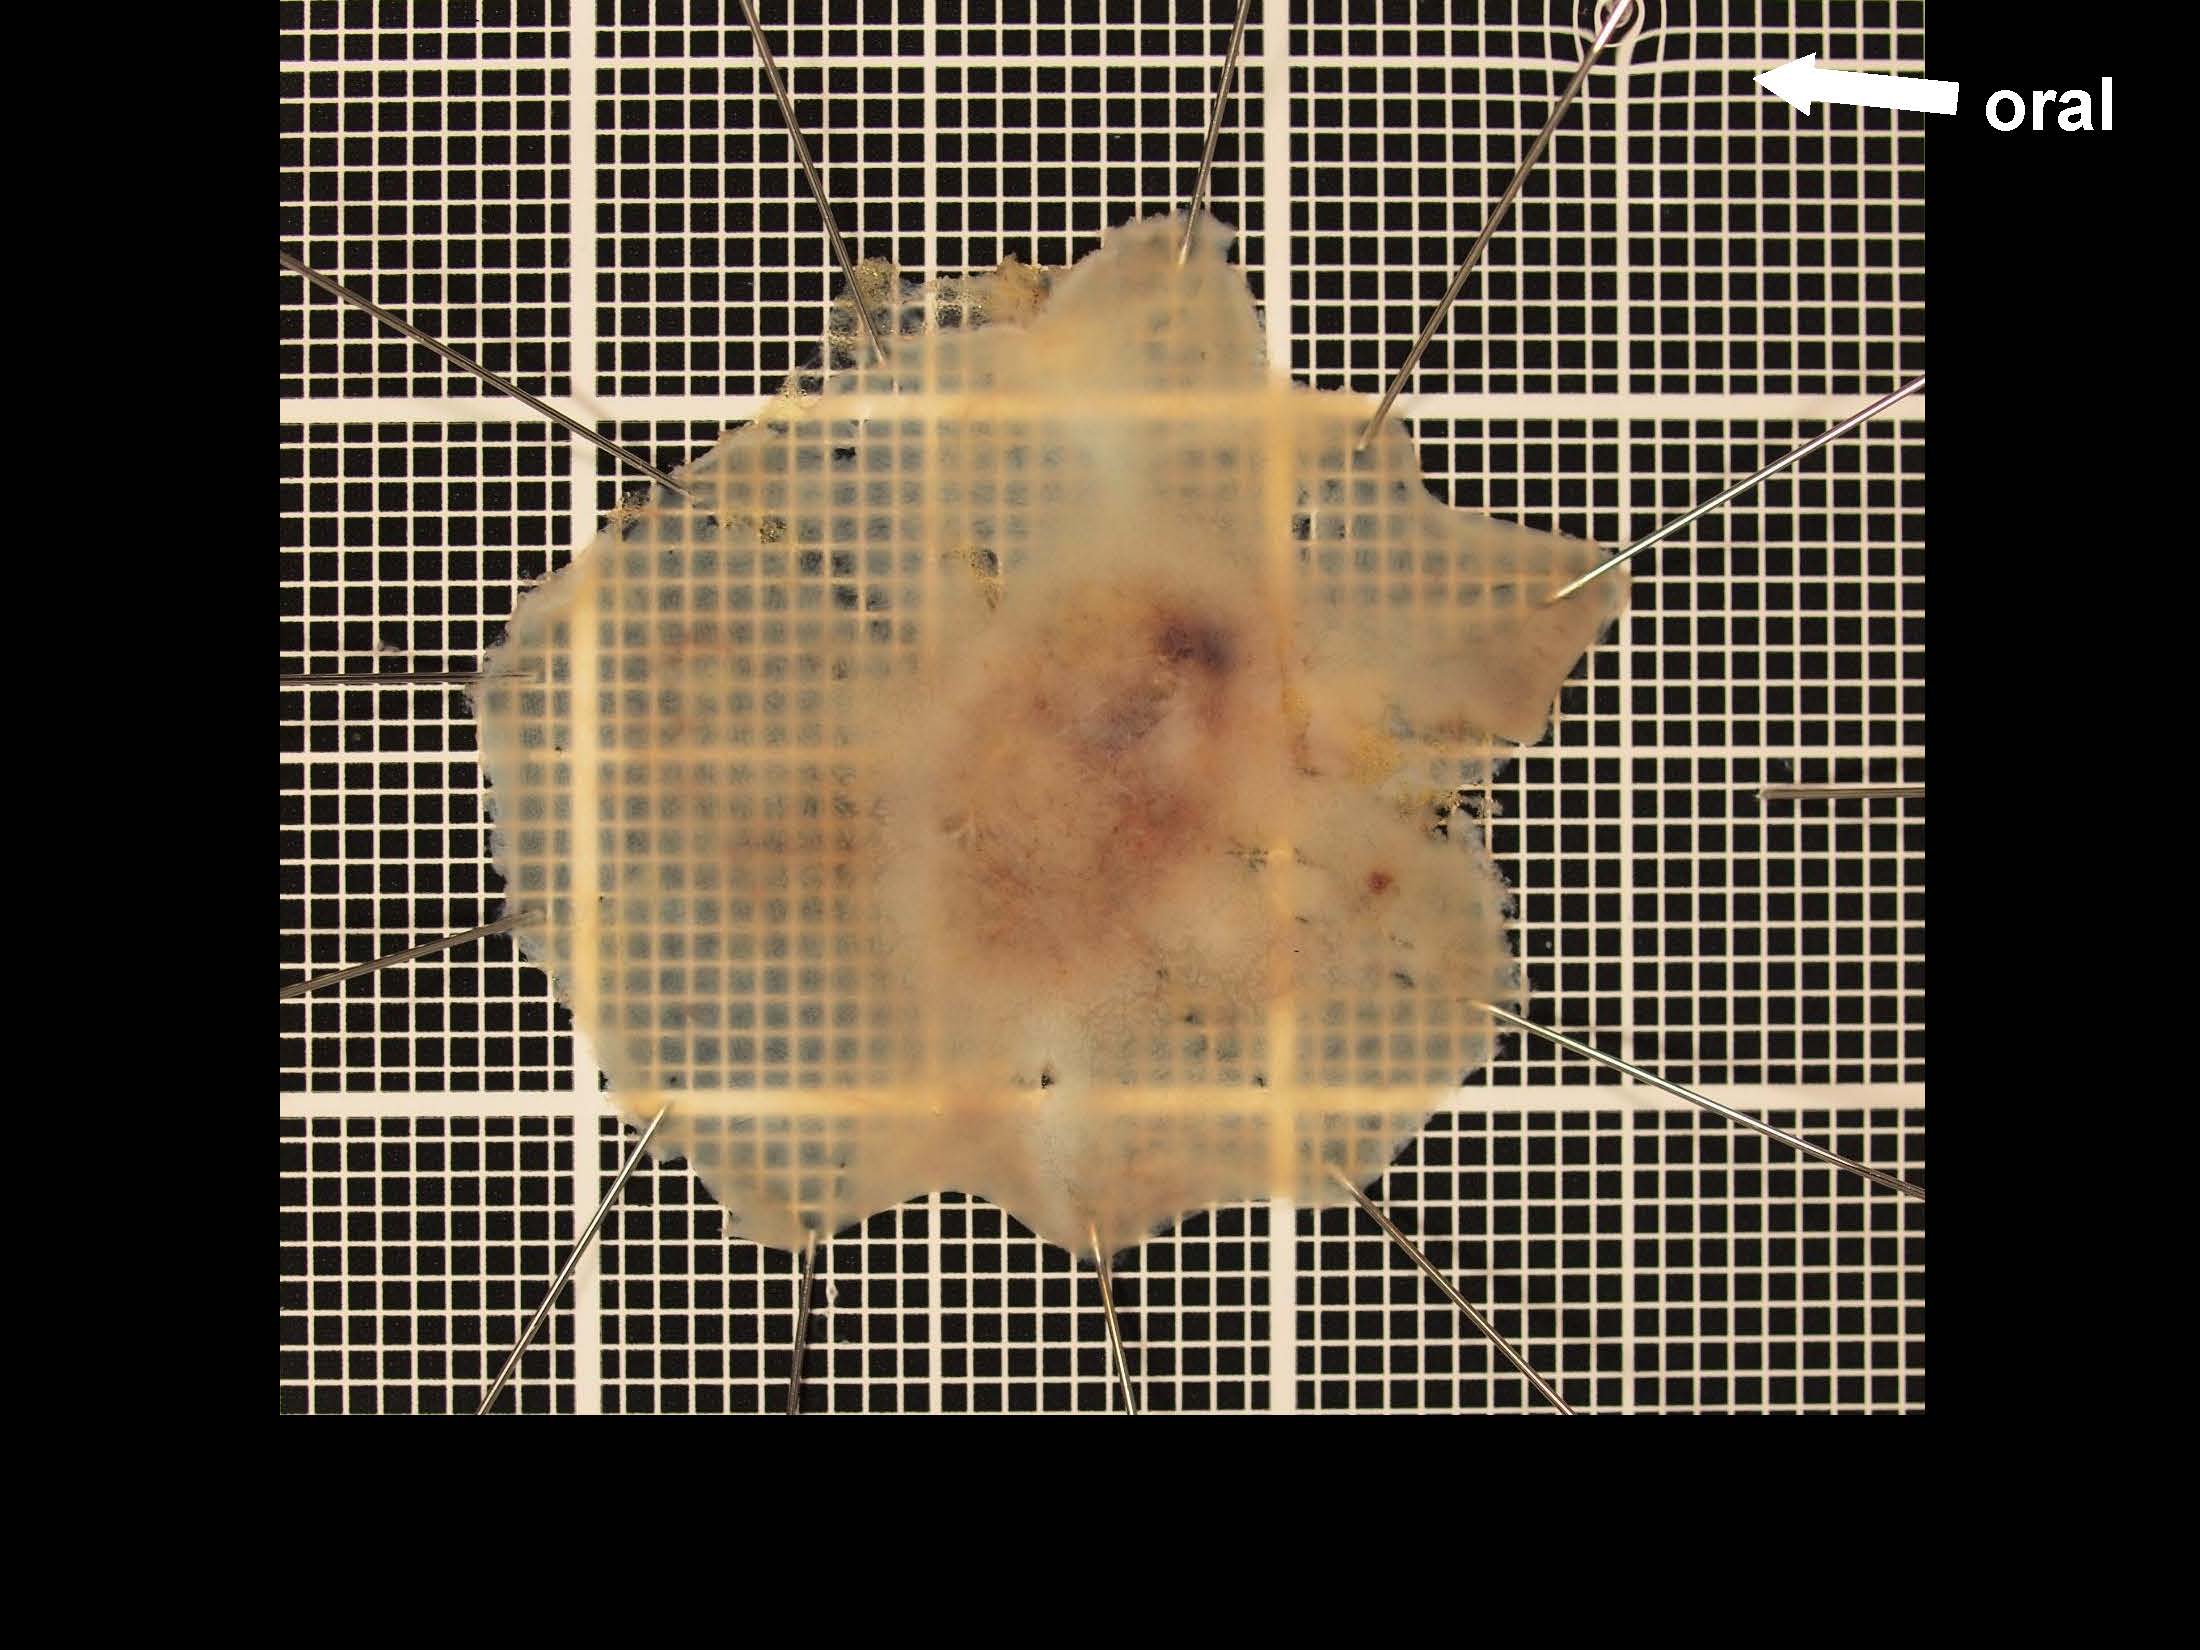

消化管Mapping~大腸~ 2021.10.27

消化器センター 消化器内科

消化管Mapping

消化管Mapping~大腸~

内視鏡検査・治療